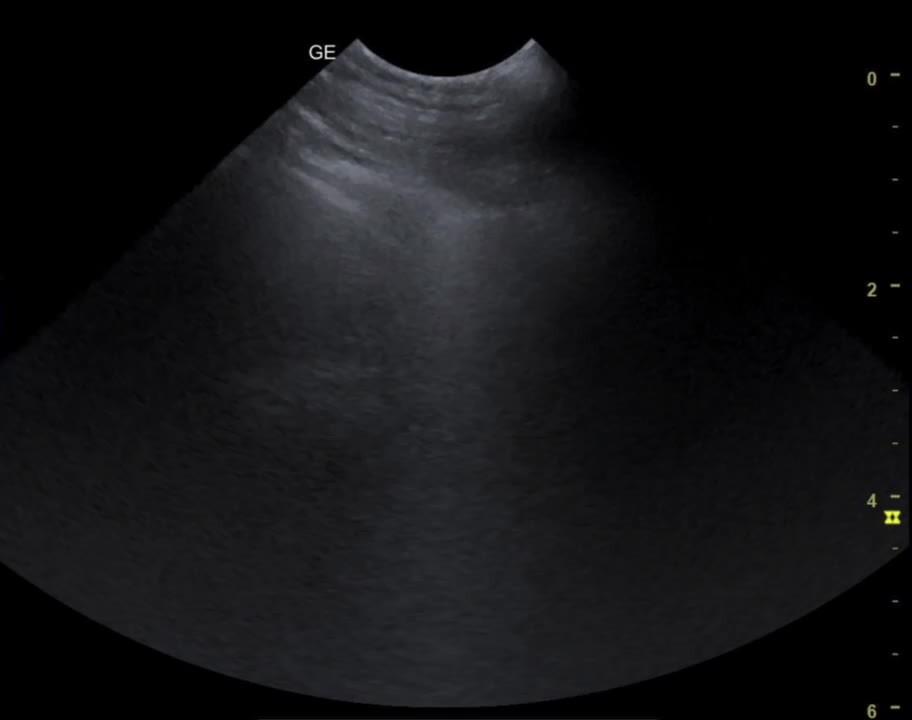

B-lines, lung ultrasonogram

B-lines are bright (hyperechogenic) vertical artifacts that extend from the pleural interface through the screen. They indicate fluid accumulation within the interstitial space.

B-lines are bright (hyperechogenic) vertical artifacts that extend from the pleural interface through the screen. They indicate fluid accumulation within the interstitial space.